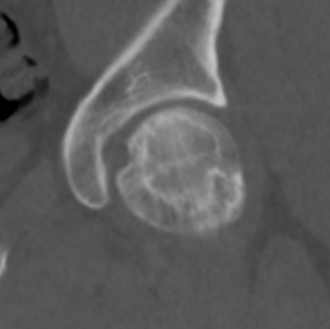

Xray

Stage II: sclerosis with cystic areas resorption, no collapse

Stage III: collapse / flattening femoral head with preserved joint space

Stage IV: Collapse with osteoarthritis

CT

Can diagnose early collapse & flattening